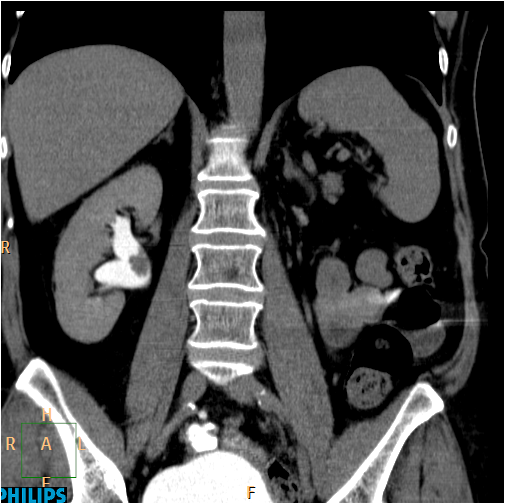

Image

Figure 6. CT image of an extensive right pelvic tumor on excretory phase coronal CT scans.